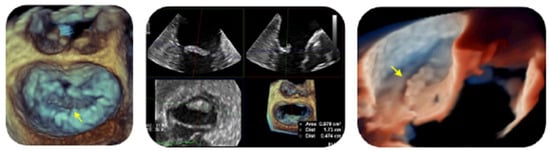

- The role of 2D and 3D-TEE for detection and characterization of NBTE valvular lesions;